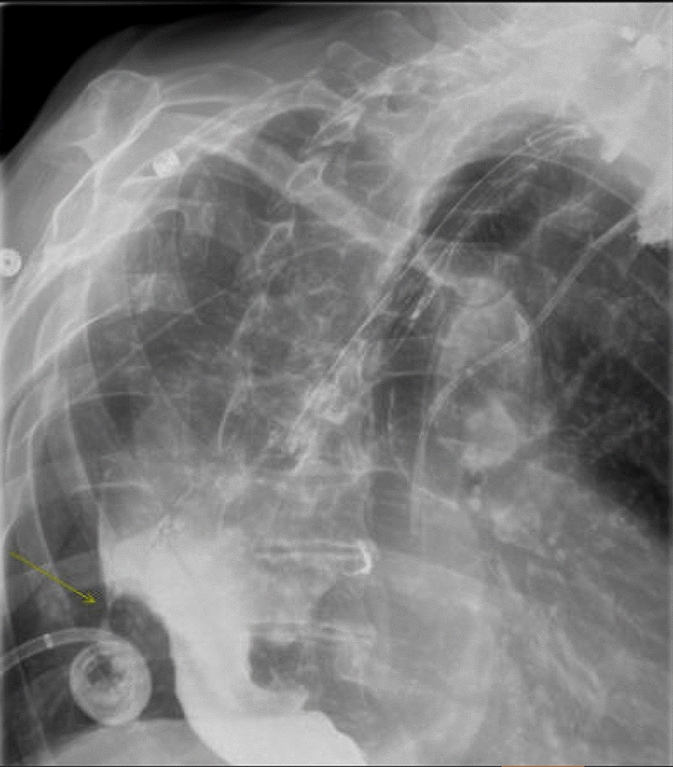

M. Carolina Jimenez, MD; Robert F. Cubas, MD; Jose M. Martinez, MD; University of Miami/Jackson Health System

Introduction: Biologic mesh has been used in clean-contaminated and contaminated fields and while wound infection rates may be high, infection is usually superficial and graft removal is unusual. Biologic mesh has been reported to have higher recurrence rates and poor incorporation into native tissue in comparison to synthetic mesh. Currently, there is no consensus on mesh preservation treatment in cases of mesh infection after hernia repair.

Methods: We present a 72-year-old male with prior radical cystectomy and neobladder creation complicated at the time by neobladder-cutaneous fistula and wound infection requiring revisional surgery and incisional hernia repair with mesh. He developed a large recurrent incisional hernia and underwent open hernia repair with bilateral anterior component separation, extensive lysis of adhesions, removal of prior mesh, and placement of a biologic mesh (Strattice™ RTM) in an underlay and onlay fashion. Intraoperatively, the defect measured 20 cm long by 14 cm wide. Postoperatively, he was treated for neobladder infection and CT cystogram found no extravasation from the neobladder. He presented to the emergency department 6 weeks after surgery with spontaneous partial midline wound dehiscence, with exposure of the onlay mesh and drainage of clear fluid, which was confirmed to be urine by fluid creatinine level. Repeat CT scan demonstrated a filling defect at the anterior wall of the neobladder with contrast leaking into a contained collection interposed between the anterior abdominal wall and the underlay mesh, extending superiorly between the small bowel loops and dehiscence of the midline abdominal wound. The patient was treated with a course of antibiotics and indwelling Foley catheter and bilateral nephrostomy tubes for urine diversion.

Results: Three months later, repeat CT cystogram demonstrated resolution of the leak and the nephrostomy tubes and Foley catheter were removed. The patient has continued daily wound care with significant reduction in size of the midline wound and increasing granulation tissue around the onlay mesh. He has not required further admissions to hospital and there has been no hernia recurrence so far.

Conclusion: In the appropriate setting, contaminated biologic mesh after surgery may be treated with medical management with adequate wound closure, avoiding the need for surgery and mesh explantation.